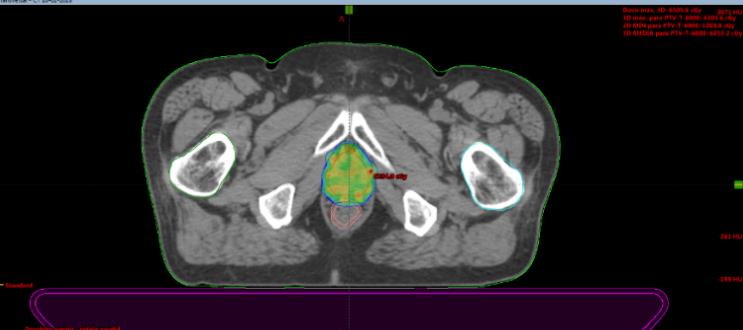

Se presentan figuras de un caso clínico de nuestro centro. Paciente de 57 años, APE: 6.5, Biopsia Gleason 7 (3+4) 2/6 sextantes. Etapificación (-), Rechaza cirugía.